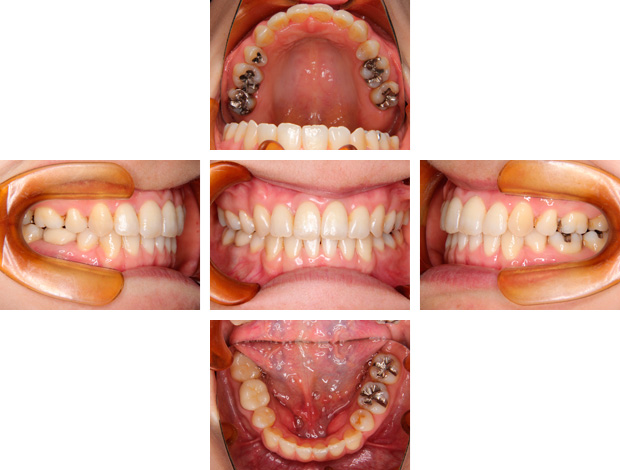

治療後

叢生、前歯の傾斜、口元の突出感があり、非抜歯で治療すると前歯の傾斜、口元の突出感は悪くなることが予想されました。

そのため話し合いの結果、上下左右第一小臼歯の抜歯を行い、三十代であったため歯周組織へのダメージを考慮しながら、約3年の期間をかけて治療した症例です。

診断名

叢生

年齢

34歳7ヵ月(女性)

装置

マルチブラケット、QH(クワドヘリックス)で上顎の側方拡大

抜歯部位

上下左右第一大臼歯(口元の状態、歯周組織への影響を考慮し、便宜抜歯を選択。)

治療期間

3年2か月